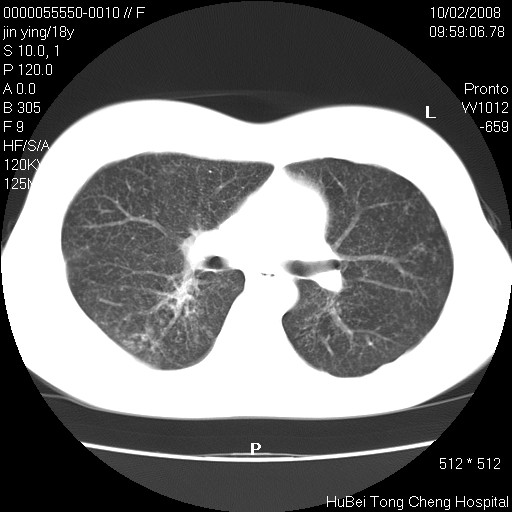

患者 女,18y。发热十余天,伴咳嗽。pe:t39⒈℃,bp 110/80mmhg,p 86次/min。神清,精神欠佳。双肺可闻及少许湿罗音。既往史不详。

临床诊断:肺部感染?

胸部ct轴位平扫(层厚10mm,螺距1.5,重建间隔10mm),图像如下: